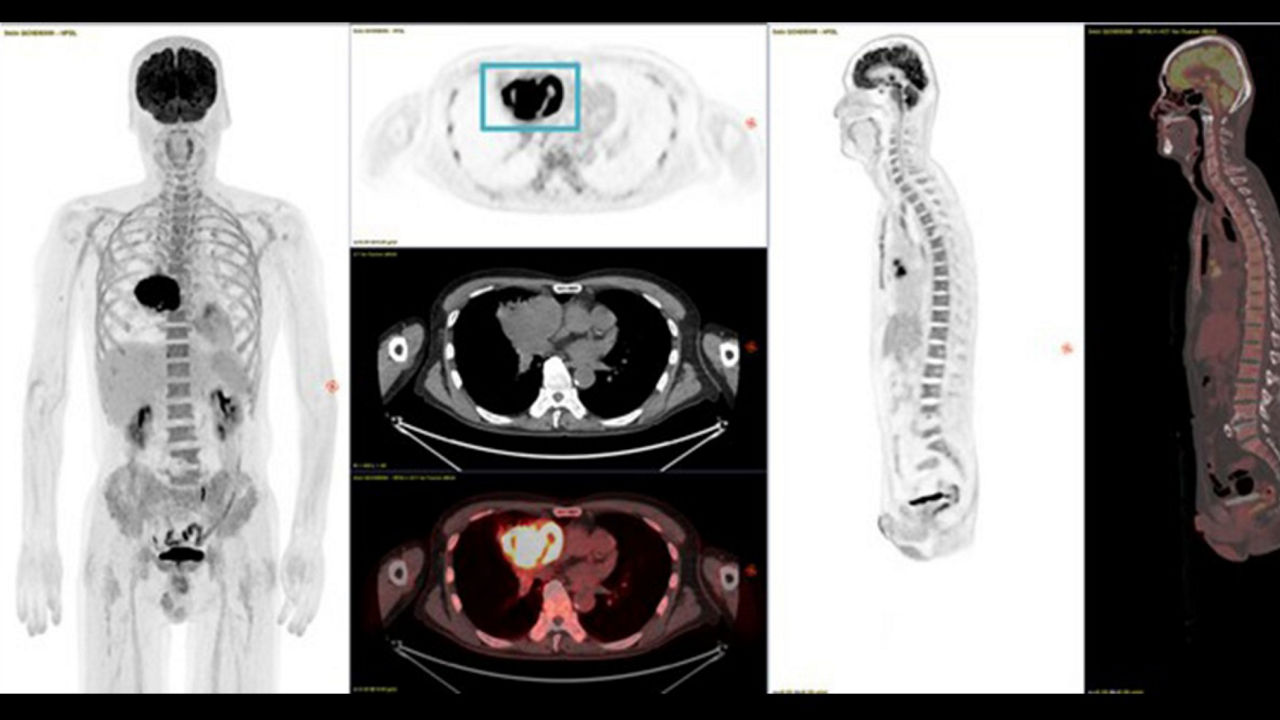

Leveraging transformational imaging technology to realize the promise of precision medicine and help deliver better outcomes. Our medical imaging products range from systems, including MRI, CT, PET, SPECT, Ultrasound, Mammography and X-ray, to digital and AI solutions to help drive healthcare digitialization, help enable faster exam workflow, improve clinical outcomes and increase efficiencies.